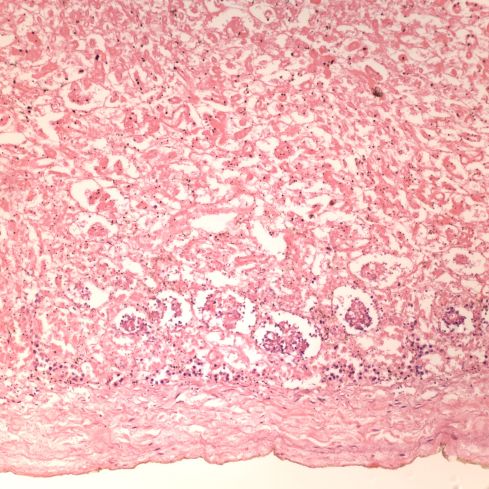

At 38 weeks of gestation the body weight is between the 3rd and 10th percentile. The placenta appears less mature than 38 weeks, the anatomic portion of the Ballard score was 36 weeks, and there may be some minimal nephrogenesis present (Figure 1). How the gestational date was determined is unknown, but it is possible that the infant is appropriate weight for 36 weeks of gestation.

Figure 1: Just beneath the capsule of the kidney on the bottom of the image, there is some preserved nuclear basophilia and the suggestion of a still transitional nephrogenesis. (20x H&E)